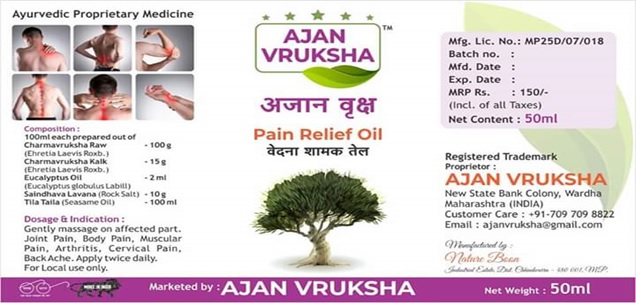

Ajan Vruksha Herbal Pain Relief Oil

अजान वृक्ष आयुर्वेदिक वेदना शामक तेल

Ajan Vruksha Herbal Pain Relief oil for Joint Pain,

Body Pain, Muscular Pain, Arthritis, Cervical Pain & Back Ache

"अजान वृक्ष आणि खंडू चक्का आयुर्वेदिक वेदना शामक तेल "

मिळवा वेदनांच्या त्रासापासून मोक्ष, वापरून अजान वृक्ष

दुखण्यावर इलाज पक्का, खंडू चक्का खंडू चक्का

वेदना सहन करू नका त्यांचा विनाष करा

सांधे दुखी, कंबर दुखी, व अश्या अनेक वेदनांवर आम्ही घेऊन आलो एकच उपचार

अधिक माहितीसाठी त्वरीत संपर्क करा 9923089064/7097098822